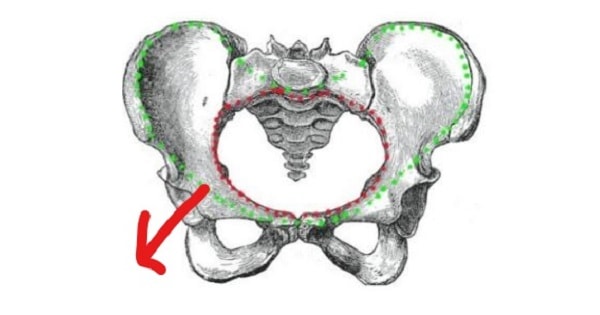

Red

True Pelvis

Green

False Pelvis

What marks the boundary of the true and false pelvis?

Pelvic Brim